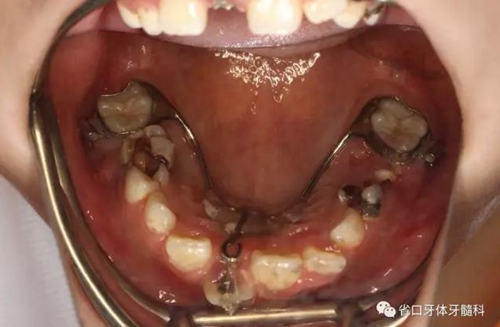

治療過程:安裝上頜腭托式牽引裝置,局麻下翻瓣、開窗、暴露11牙冠,在牙齒腭側(cè)面粘接附件進(jìn)行輕力牽引,縫合。定期(2-3周)復(fù)診加力,待11唇面暴露后粘接前牙托槽,擴(kuò)展間隙的同時(shí)繼續(xù)進(jìn)行牽引、排齊。6個(gè)月后牽引到位,術(shù)后牙齒位置和牙髓活力均正常,牙齦形態(tài)良好,X線片顯示11牙軸基本正常,牙根發(fā)育良好。牽引結(jié)束后拆除前牙固定矯治器,由于前磨牙已開始替換,因此繼續(xù)戴用腭托進(jìn)行間隙保持。

腭托式牽引裝置

局部固定矯治器進(jìn)一步牽引、排齊11